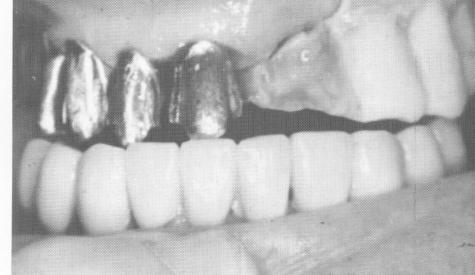

Fig. 15-33. Using the "built-up" acrylic teeth on the left side as a bite guide, metal copings were cast and fitted over the teeth on the right side.

2 Metal copings are cast and fitted over upper teeth on right side